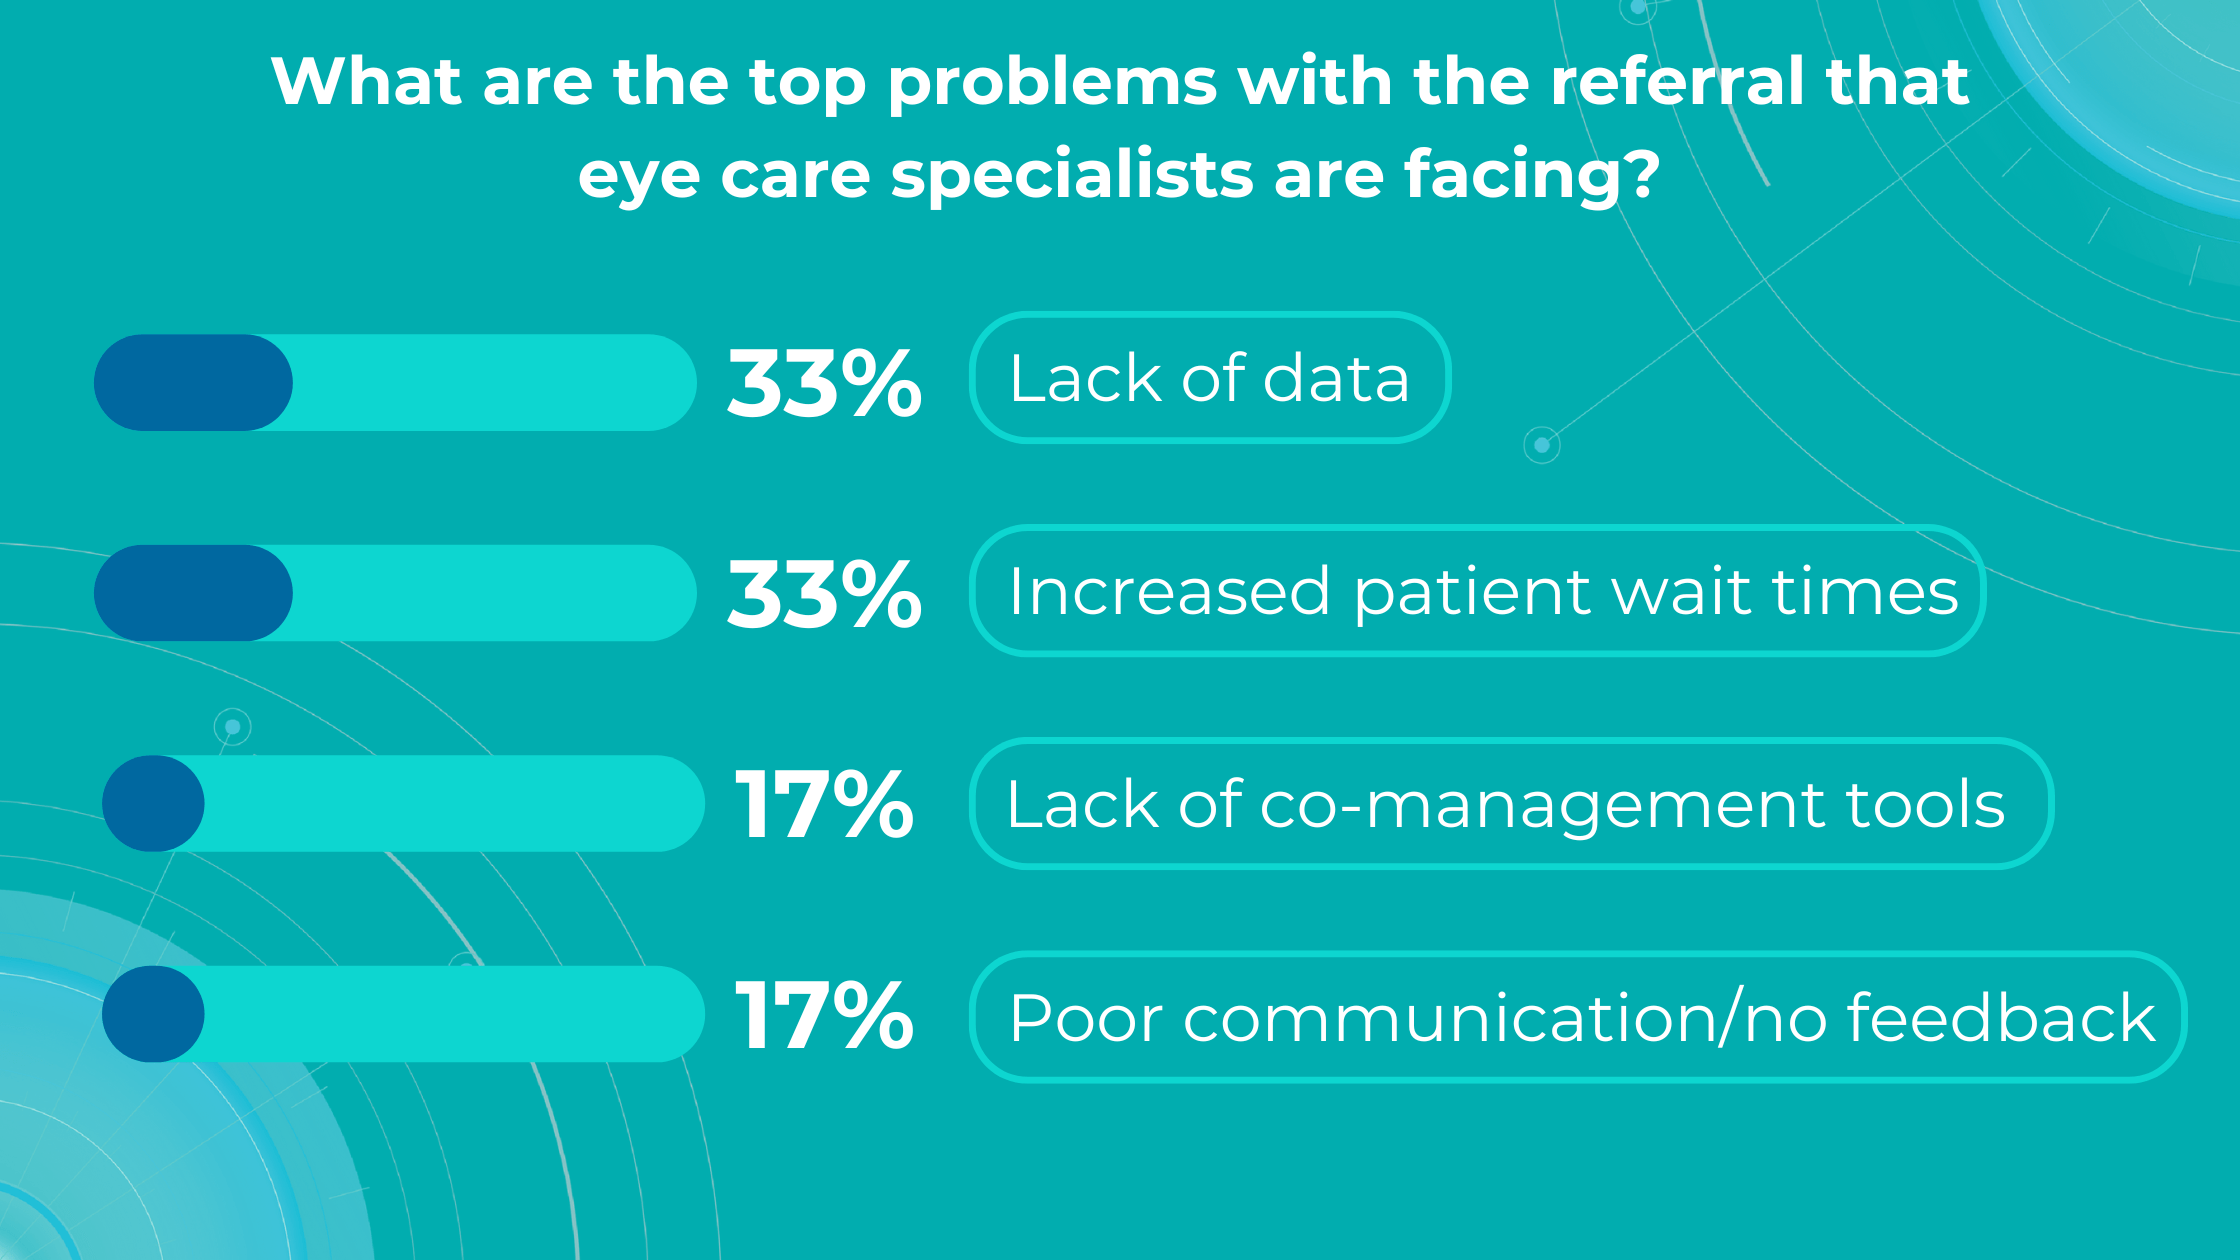

Altris AI’s survey identified a lack of data and increased patient wait times as the top problems with referrals for practitioners, while lack of co-management tools and poor communication/feedback ranked lower.

Optometry referral: top problems